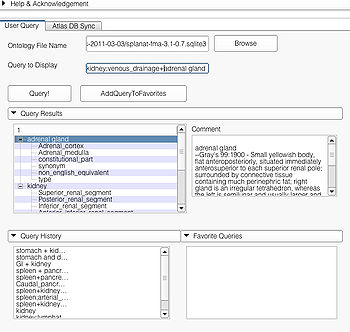

User Query Page

This page is useful for creating visualizations based on user typed queries. The user inputs consist of the Ontology File Name and Query To Display. The button Query fires a query and causes the module to start processing the user query for visualization. The button AddQueryToFavorites adds the last typed user query to the list of favorite queries. The favorite query list is shown in the bottom panel Favorite Queries. Additionally, the interface also shows a history of typed queries in the panel Query History.

The Query Results panel shows the result of a query, consisting of all the associated predicates and parts for the query. The Figure User Page GUI shows the result of a simple query "limbic system".Additionally, the interface also shows a Comment that contains any relevant textual information about the query obtained from the ontology. The user can refine a search by selecting from the query result. Optionally, the user can also select by clicking on any selection from the Query History or Favorite Queries panel to redo search and visualization. The interface supports the multiple selections to form complex queries. The visualization resulting by searching with the query "Limbic system" is shown below.

Specialized Queries

A specialized query helps to search for a query with additional constraints typically using an ANDing operation. Specialized query is specified using a ";" between the search terms. In terms of search in the ontology, the ";" will either result in a search involving the first term as the Subject or Object and the second term as the Predicate(e.g. "straight gyrus;synonym"). In the case where the second term is not a predicate but a part of the preceding term, e.g. "limbic system;Fornix", the visualizer logic automatically detects that the succeeding term is an individual search term and produces the visualization using the succeeding term as the search string resulting in the visualization of query "Fornix".

Specialized queries can be combined with other simple or specialized queries to form complex queries (e.g. "motor system + straight gyrus;synonym"). An example of a complex query using specialized and simple query terms is shown below.

Query Interface

The user can query by typing the query in the Query to Display box or by selecting from one of Query Results, Query History, and Favorite Query panels. All the panels support multiple selection. Multiple selection will result in a complex query. An example of multiple selection from the Query Results panels is shown below. However, it is not possible to create a complex query by selecting from multiple panels (e.g. selecting "some string in Query Results" and "some other string in Query History").

Selecting a string from the Query Result panel will result in creating a specialized query. Example of such a selection is shown below. Multiple selections from the "Query Result" pane will result in a complex query using specialized query terms as shown.